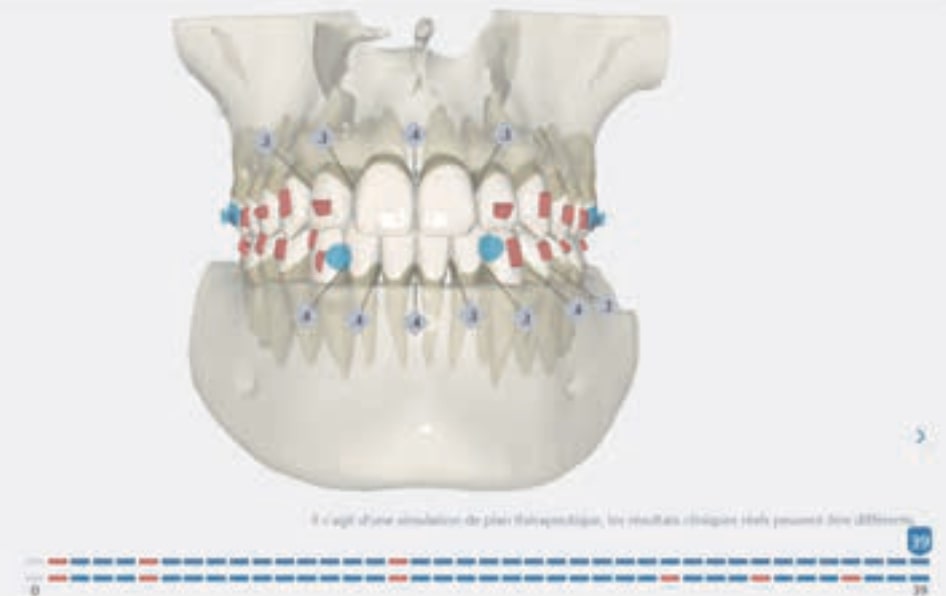

Treatment setup